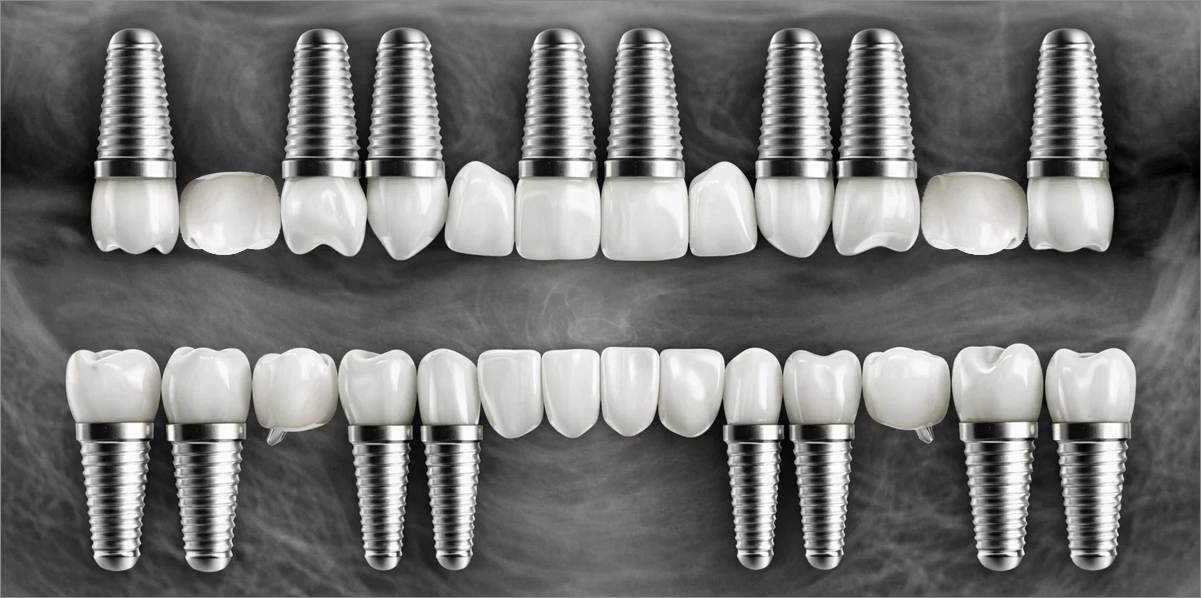

In full-mouth implant cases, implants are placed only where needed, and the remaining gaps are restored using a bridge (pontic) method — minimizing the total number of implants while achieving masticatory force comparable to natural teeth, helping to reduce the financial burden.

Full-mouth implant restoration is categorized into full placement or minimal placement approaches.

Full PlacementUsing a method of placing 8–9 implants in the maxilla and 8 implants in the mandible, this approach fully restores all 28 natural teeth, creating an oral environment most closely resembling

Minimal PlacementUsing a method of placing 6–7 implants in the maxilla and 6 in the mandible, this approach restores both posterior and anterior teeth, efficiently rehabilitating the entire oral cavity.